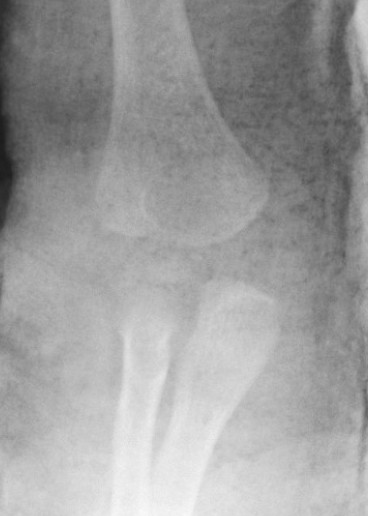

Xray

Distal physis not ossified < 1 year

- radius and ulna lose normal association with distal humerus

- posteromedial displacement of the ulnohumeral joint

- appears like an elbow dislocation

- disruption of radio-capitellar line